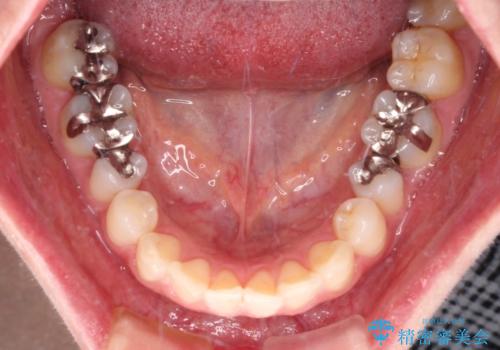

- 銀歯をセラミックにしたいとのことで来院された患者様です。

まず麻酔をして銀歯を外し、むし歯を除去し、形を整えて型取りします。

そして次の来院時、セラミックインレーを装着し、噛み合わせなどの調整を行います。

それを左右に分けて行いました。